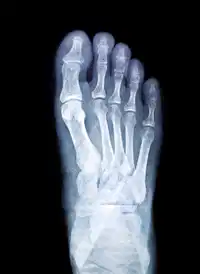

Identify

Identify: